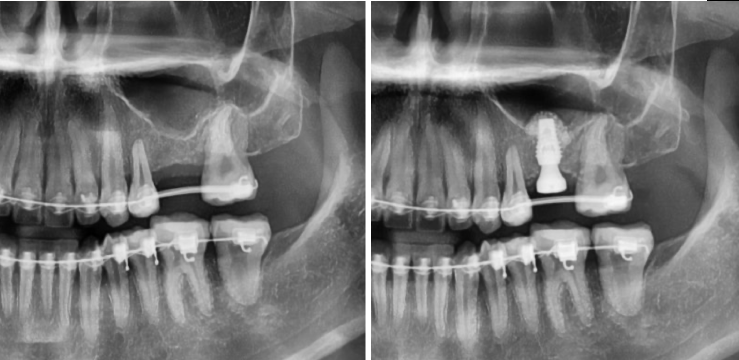

"윗 잇몸뼈가 부족해서 상악동 수술이 필요하다"는 이야기를 들어본 적 있으신가요? 임플란트 식립 시 윗니 어금니 부위의 잇몸뼈가 충분하지 않을 때 필요한 시술이 바로 상악동 수술(상악동 거상술, 상악동 뼈이식)입니다. 이백점치과는 고난이도 상악동 수술도 안전하고 성공적으로 진행하여 환자분들께 건강한 임플란트를 선사합니다. CASE. 20대 여성 환자 "잇몸뼈가 부족해요" 임플란트 고민 ○ 환자분의 고민: 왼쪽 위 어금니 임플란트를 희망하며 교정치과로부터 의뢰되어 내원하셨습니다. ○ 진단: 임플란트 식립에 필요한 잇몸뼈(일반적으로 8~10mm 길이의 임플란트 식립)가 4~5mm로 턱없이 부족 한 상태였습니다. ○ 치료 계획: 부족한 잇몸뼈를 확보하기 위해 상악동 막을 안전하게 들어 올린 후 뼈이식을 진행하는 상악동 수술 을 계획했습니다. ![]() 이백점치과의 정교한 상악동 수술 과정 상악동 수술은 상악동 막을 손상 없이 거상하고 뼈이식을 진행하는 정밀한 시술입니다. 1. 정밀 진단: CT 촬영을 통해 남아있는 잇몸뼈의 양과 상악동의 상태를 면밀히 분석합니다. 2. 상악동 거상 및 뼈이식: 부족한 잇몸뼈 부위에 상악동 막을 조심스럽게 들어 올린 후 충분한 양의 뼈를 이식합 니다. 이로써 임플란트 식립에 필요한 충분한 잇몸뼈 공간을 확보합니다. (예: 4~5mm 남아있던 잇몸뼈에 4~5mm 추가 뼈이식으로 8~10mm 확보) 3. 임플란트 식립: 뼈이식을 통해 확보된 충분한 잇몸뼈에 임플란트를 정확한 위치와 각도로 식립합니다. ![]() 성공적인 결과와 빠른 회복 수술 후 CT 촬영을 통해 기존 잇몸뼈 위로 상악동이 잘 올라가고 새로운 뼈가 성공적으로 이식되었음을 확인했습 니다. 또한 임플란트가 정확하게 식립되었음을 검증했습니다. ![]() 상악동 수술 후 임플란트 크라운(보철물)은 보통 3~6개월 뒤에 완성됩니다. 이 기간은 환자분의 남아있는 잇몸뼈양에 따라 달라질 수 있습니다. 본 환자분은 4개월 뒤 성공적으로 본을 뜨고 임플란트 크라운까지 장착 완료하여 건강하고 기능적인 치아를 되찾았습니다. ![]() 상악동 수술, 숙련된 의료진에게 맡겨야 하는 이유 상악동 수술은 출혈, 상악동염, 상악동 천공 등 다양한 합병증이 발생할 수 있는 고난이도 시술입니다. 따라서 외과 적인 수술 경험이 풍부하고 임플란트 보철에 대한 깊이 있는 이해를 가진 숙련된 의료진을 만나는 것이 무엇보다 중요합니다. 이백점치과는 수많은 임상 경험과 정교한 기술력을 바탕으로 고난이도 상악동 수술까지 안전하게 진행하며, 환자분들이 믿고 맡길 수 있는 최상의 진료를 제공합니다. 당신의 건강하고 아름다운 미소를 위해 이백점치과가 함께하겠습니다. |